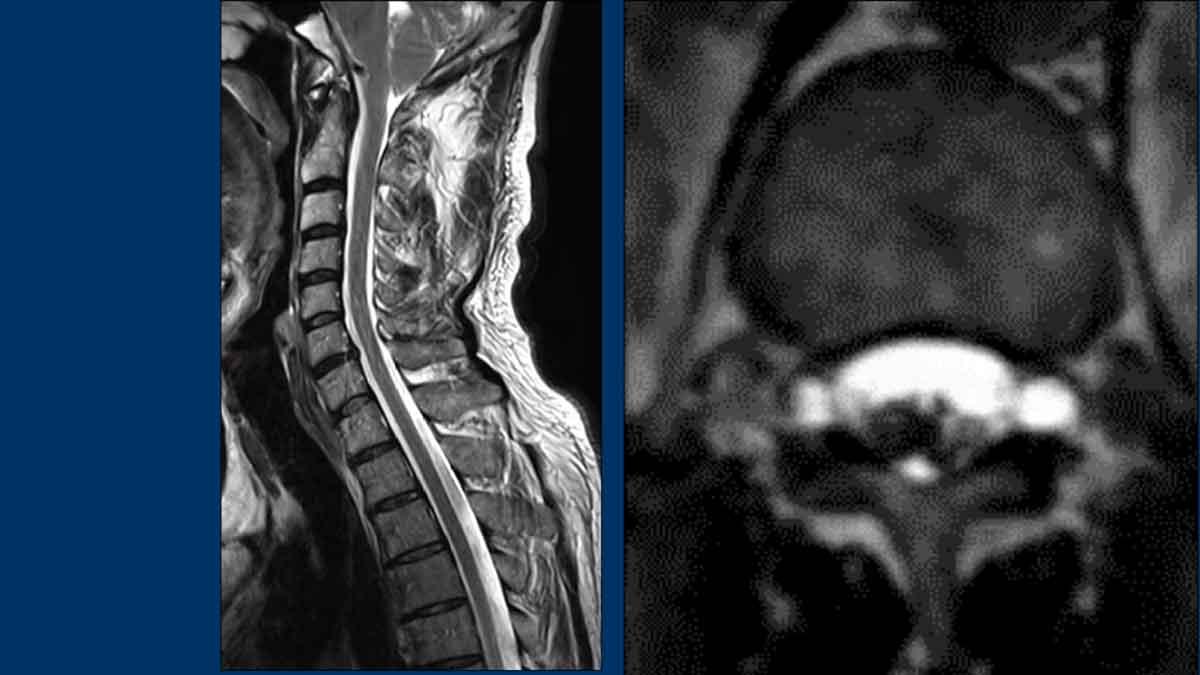

Hình ảnh

- Chuỗi xung T2W sagittal cột sống cho thấy khối tụ dịch dọc phía trước cột sống (SLEC), nằm ngay phía trước màng cứng mặt trước (cấu trúc tuyến tính màu đen được chỉ bởi các đầu mũi tên).

- Chụp tủy đồ CT thông thường (thực hiện sau chụp tủy đồ động) cho thấy hai thoát vị đĩa đệm vôi hóa một phần ở đoạn cột sống ngực trên (mũi tên).

Tiếp tục xem các lát cắt axial tái tạo của chụp tủy đồ CT…

Trên chụp tủy đồ CT thông thường, có hiện tượng rò rỉ thuốc cản quang iod vào khoang ngoài màng cứng phía trước.

Lưu ý rằng dấu hiệu này chỉ thấy được trên các lát cắt axial tái tạo (đầu mũi tên).

Trên các lát cắt sagittal, dấu hiệu tinh tế này có thể bị bỏ sót.

Hình ảnh cột sống không ghi nhận ổ dịch ngoài màng cứng dọc trục.

Tuy nhiên, tại mức L1 có ghi nhận sự bất đối xứng nhẹ (mũi tên).

Hình ảnh này nghi ngờ một ổ dịch ngoài màng cứng bên nhỏ ở phía bên phải.

Trên hình ảnh chụp tủy đồ cột sống động, ghi nhận hiện tượng rò rỉ thuốc cản quang ở phía bên phải từ một túi thừa bên.